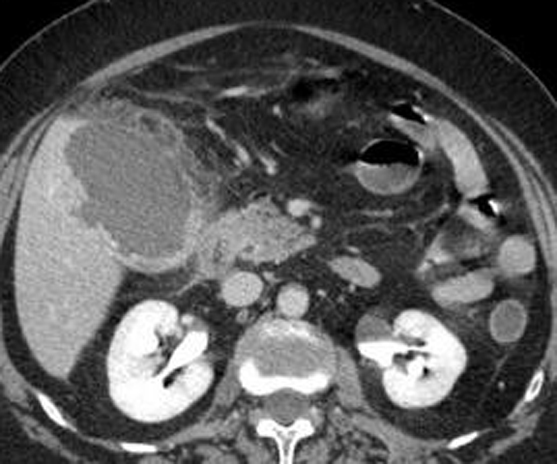

Image une cholecystite

aigue avec vesicule distendue , paroi vesiculaire

est tres epais et images de oedemes de la sous

sereuse . Coupe TDM axiale a contrast

intraveineuse |

Meme cas en coupe frontale (

coronal ) . Images de oedeme sous sereuse et

epanchement perivesiculaire et canal cystique est en

vue nette |